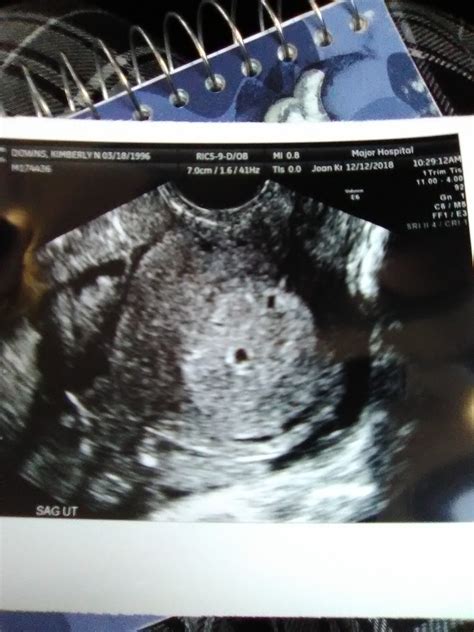

A 5 Weeks Ultrasound is typically performed transvaginally, which means the ultrasound probe is inserted into the vagina to get a clearer image of the uterus and the developing embryo. At this stage, the embryo is still very small, often measuring less than a millimeter. The primary goal of this ultrasound is to confirm the presence of a gestational sac and to ensure that the pregnancy is progressing normally.

At 5 weeks, the embryo is still very small, and the ultrasound images may not be as clear as they will be in later weeks. However, the following structures can often be visualized:

• Gestational Sac: This is the earliest structure that can be seen on an ultrasound. It appears as a small, fluid-filled sac within the uterus.

• Yolk Sac: In some cases, the yolk sac may be visible. This sac provides early nutrition to the embryo.

• Embryo: The embryo itself may be too small to see clearly at this stage, but its presence can sometimes be detected within the gestational sac.